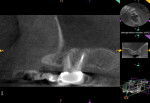

The patient underwent a CBCT study (Kodak 9000, Carestream Dental, carestreamdental.com) for further evaluation of the area (Figure 2). The 3D scan revealed thickening of the mucous membrane of the maxillary sinus, indicating severe chronic sinusitis and a large periradicular radiolucency at the apices of No. 14 (Figure 2). The pulpal diagnosis of tooth No. 14 was necrotic and the periapical diagnosis was chronic apical periodontitis.